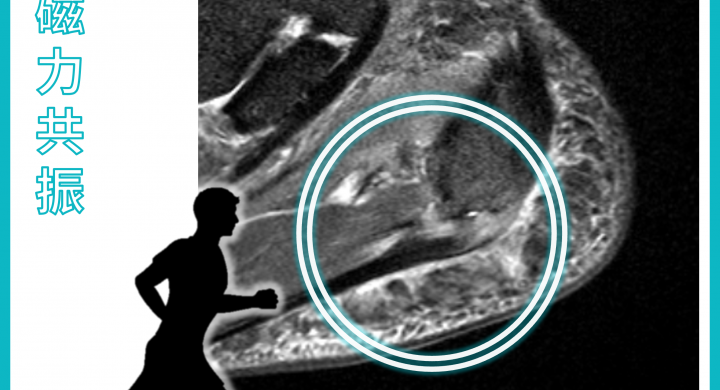

Magnetic Resonance Imaging (MRI): Plantar Fasciitis

An active runner felt pain in his heel after the Marathon. His MRI images showed swelling and inflammation in the plantar fascia near its calcaneal atta...